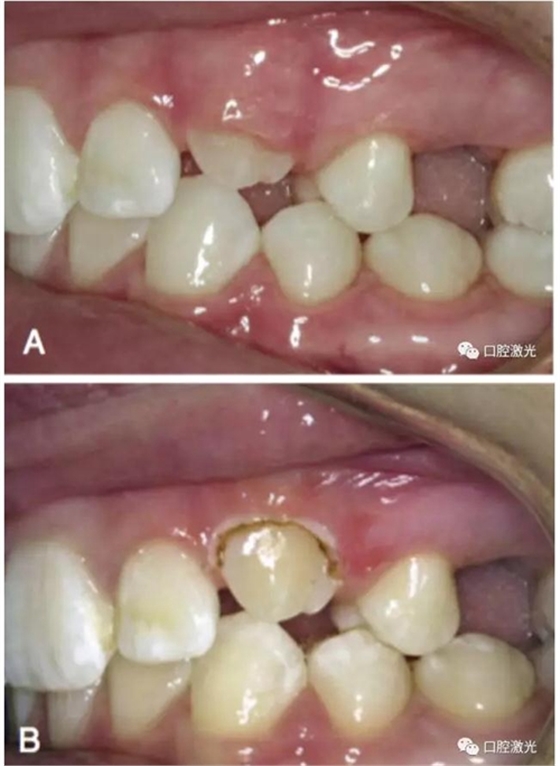

正常情況下,理想的托槽粘接位置為牙冠的中心位置。如果要達到這一目的,正畸牙醫(yī)首先需要能夠從視覺上觀察清楚牙冠的整體形態(tài)。如果存在牙齦覆蓋、遮擋的情況,就很難達到這一目的。這時,簡單的激光牙齦切割就可以很好的增加牙冠的暴露程度,達到更加準(zhǔn)確的粘接托槽的目的,從而也就加快了整個正畸療程的速度。通過下圖的病例可以看到,不僅患者節(jié)約了數(shù)月的等待時間,同時也創(chuàng)造了一個干凈的口腔環(huán)境,降低了在后續(xù)的正畸治療中可能導(dǎo)致牙齦增生的風(fēng)險。

治療前

激光牙齦切割后暴露更多的上前牙便于粘接托槽

當(dāng)天粘接托槽后即刻

4周后即可見明顯效果